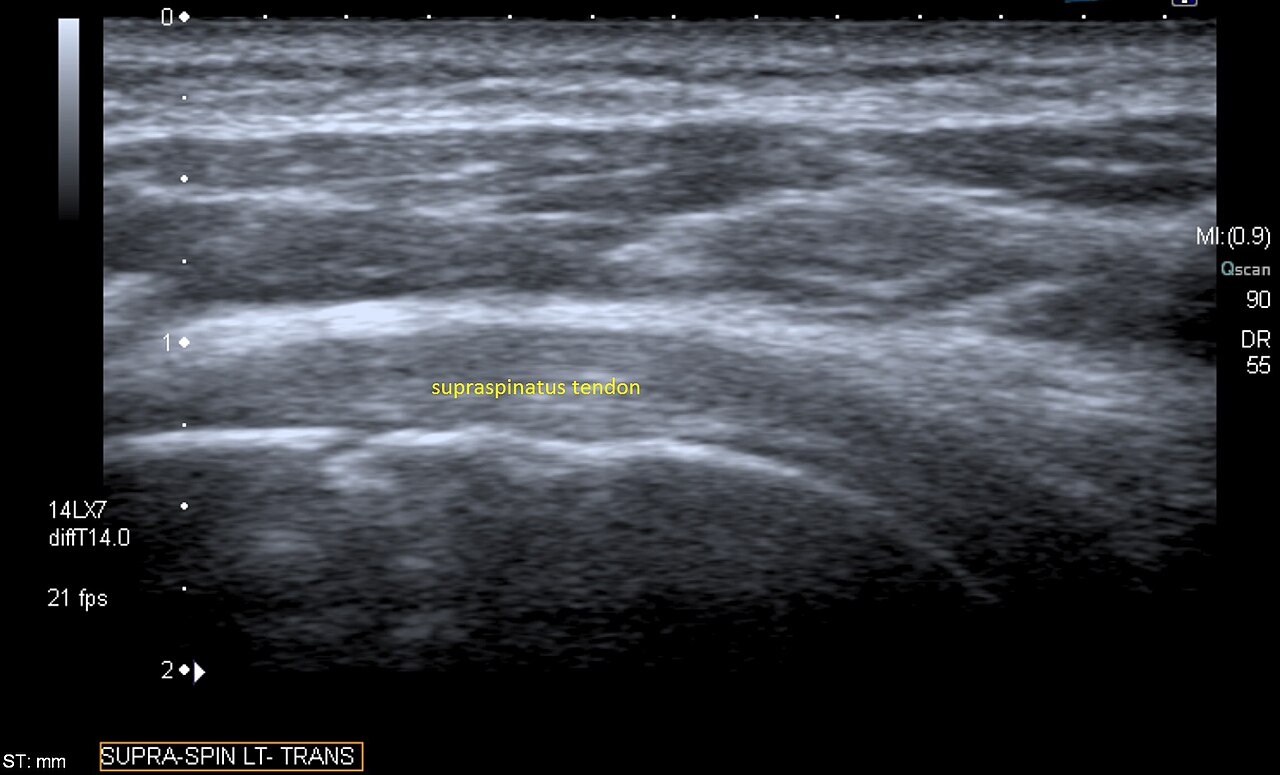

Shoulder phantom with humeral head, glenoid, rotator cuff tendons, labrum, and biceps tendon